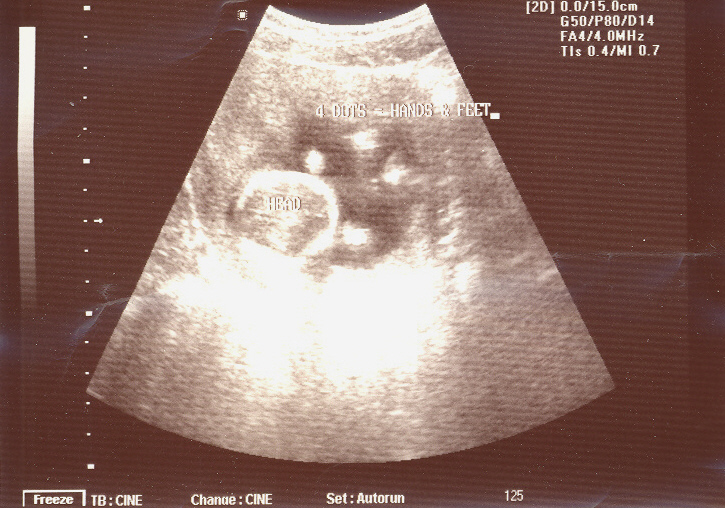

Previous Our Tiny Baby Next